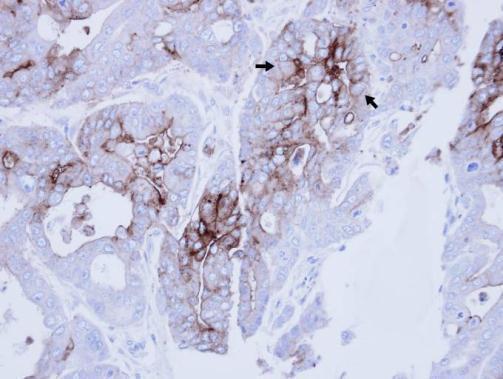

Supportive validation

- Submitted by

- GeneTex (provider)

- Main image

- Experimental details

- Immunohistochemical analysis of paraffin-embedded NCIN87 xenograft , using CEACAM6 (GTX112679) antibody at 1:100 dilution.